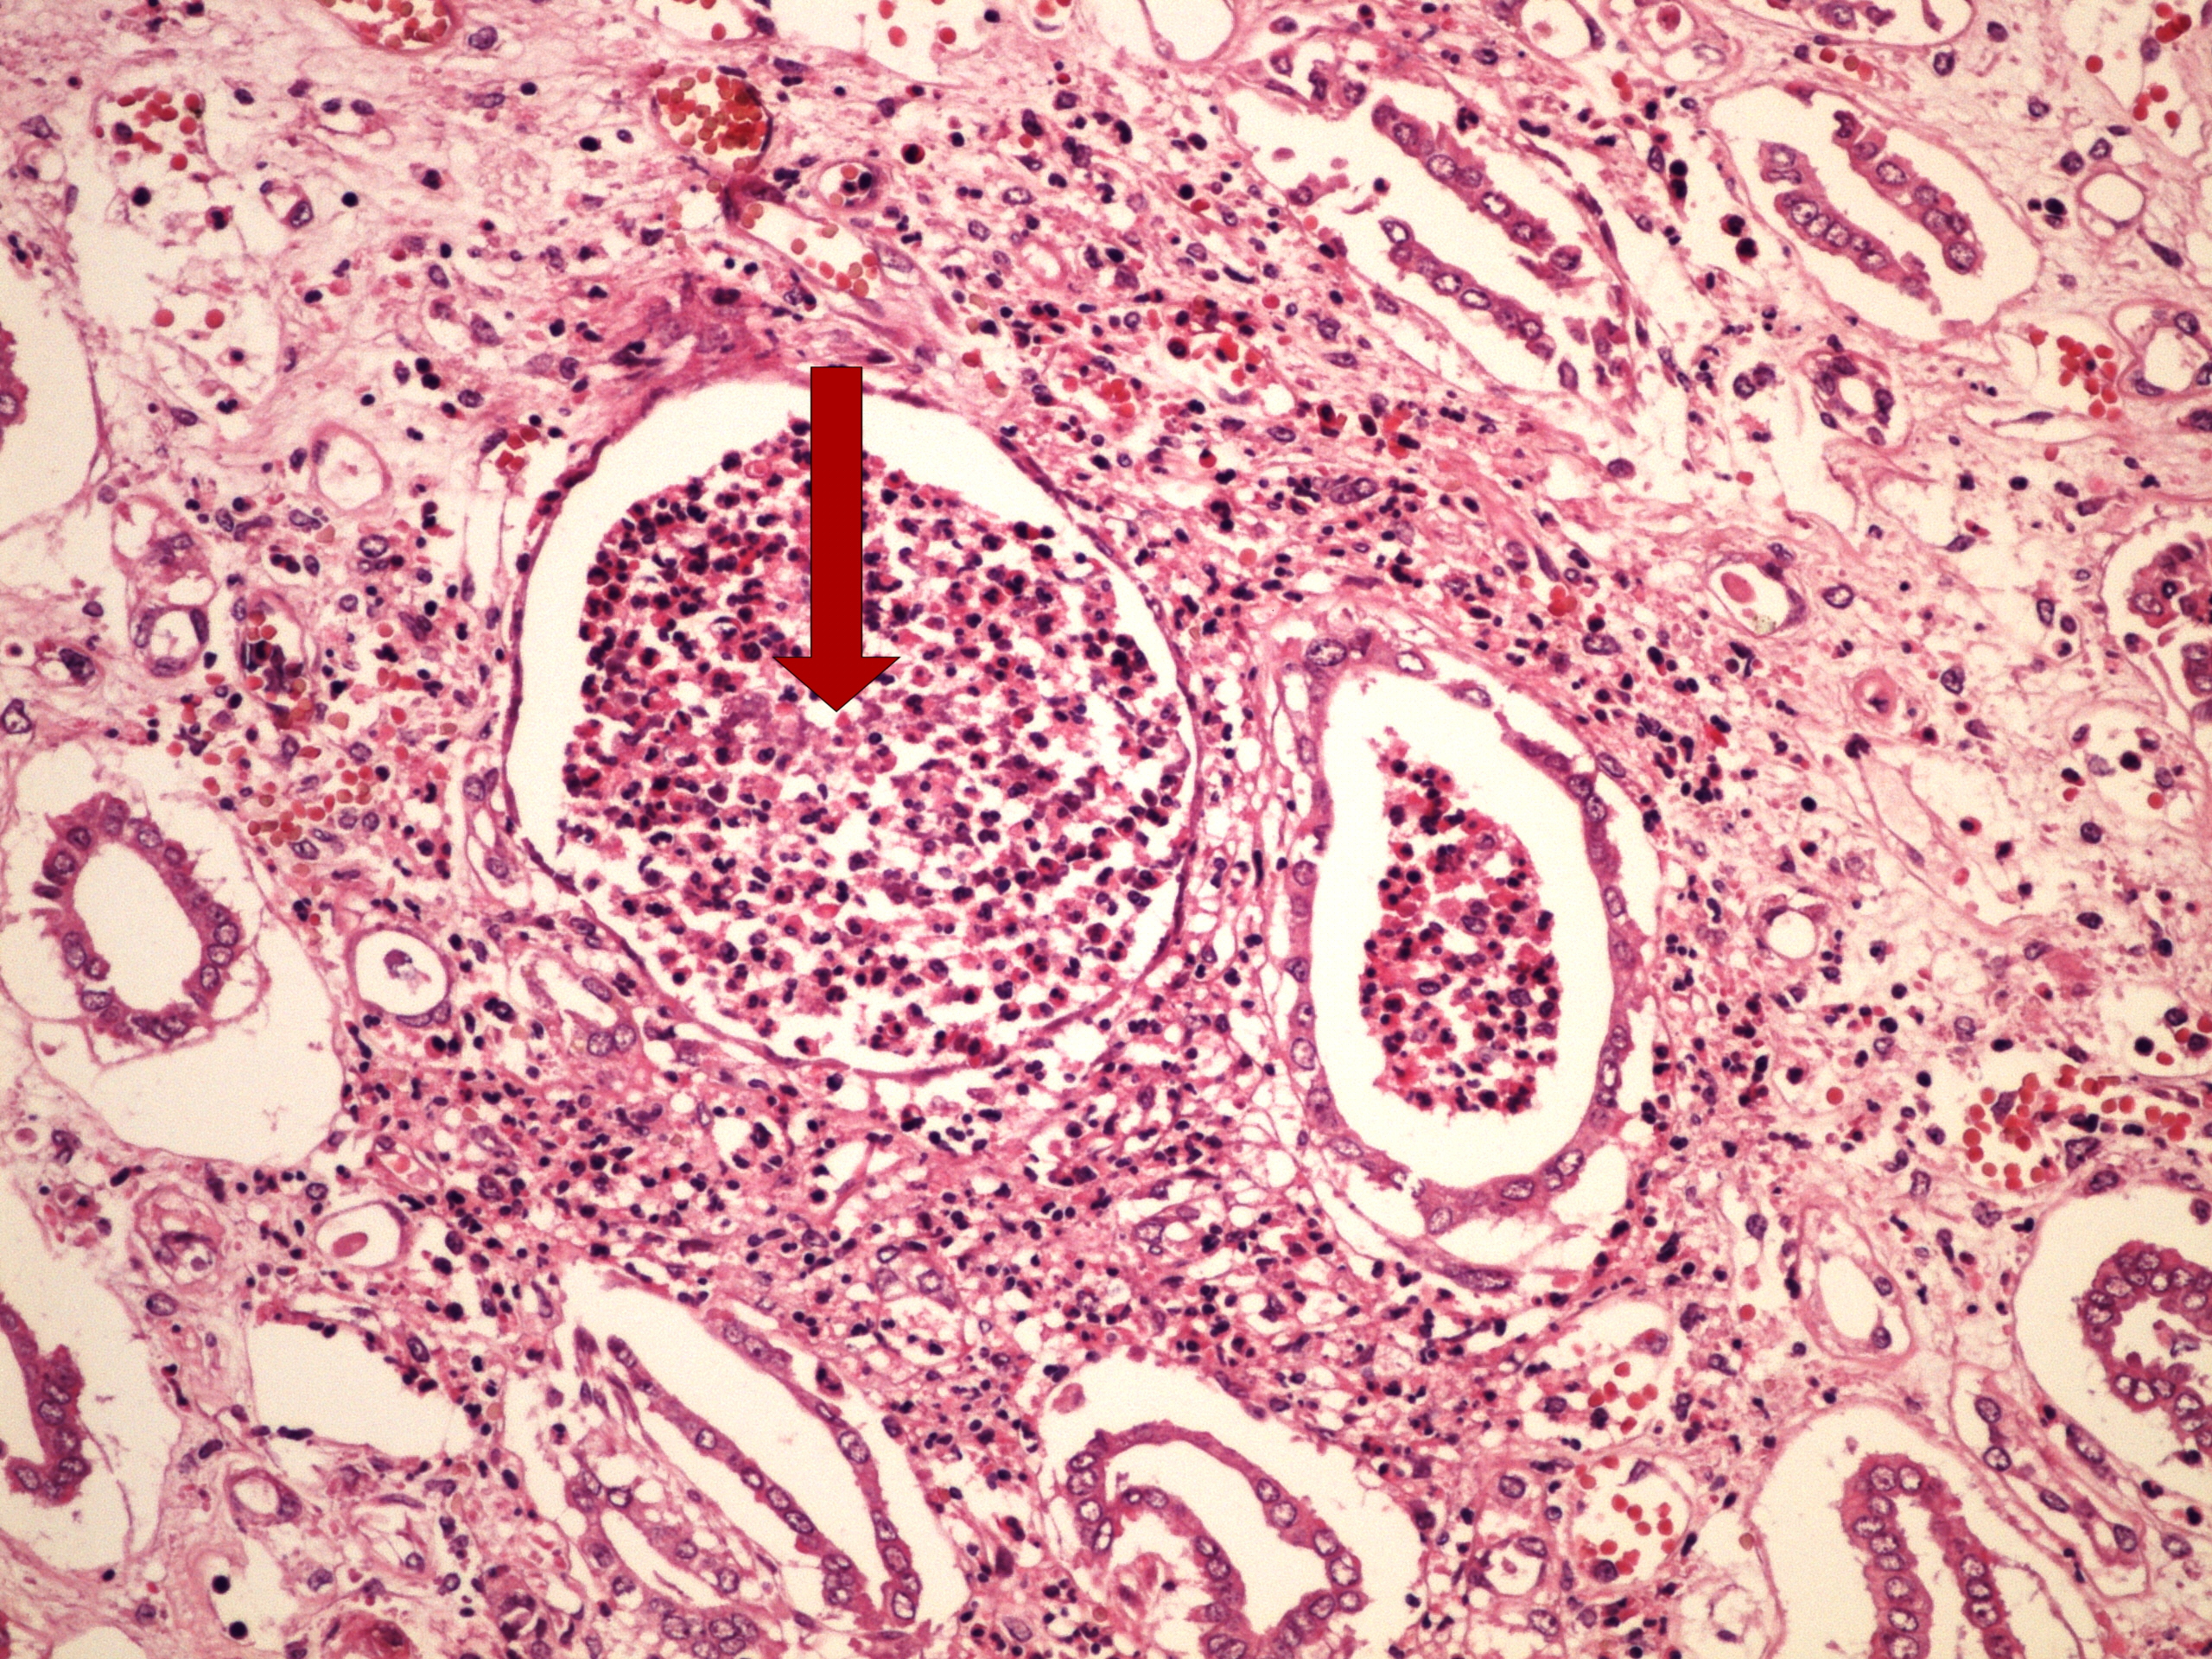

Preparát č.7 a č.8 - akutní abscedující pyelonefritis

Struktury

- glomeruly s granulocyty

- glomerulus se zánětlivým infiltrátem